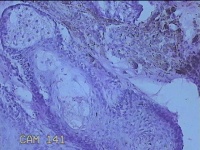

右侧颜面部结节

性别

男

年龄

41岁

临床诊断

皮下结节

一般病史

发现右侧颜面部结节20余年。

标本名称

大体所见

灰白暗红色组织1x0.3x0.2cm一个,表面带梭形皮肤1x0.3cm,皮下见结节0.8x0.3x0.2cm一个,切开挤呈实性,切面灰白粉红色,质中。